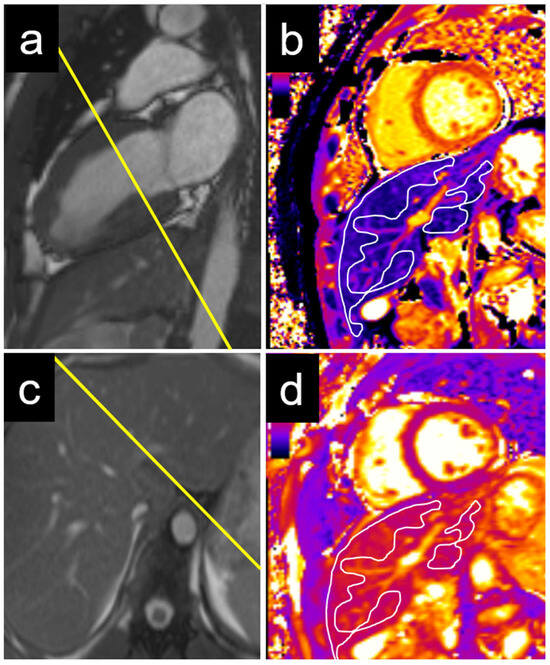

An echocardiographic evaluation revealed similar results, with significant differences in the T1 values between patients with elevated and non-elevated left ventricular filling pressures in the caudate and right liver lobes, but not in the left lobe or liver dome (Table 3). Examples of the liver T1 and T2 measurements are provided for a patient with normal NT-proBNP levels (Figure 3) and for a patient with elevated NT-proBNP levels (Figure 4).

Figure 3. Example of a 22-year-old male patient with normal NT-proBNP. The measurements were performed on a basal short axis view (a) in the caudate and right liver lobe T1 (c). The liver T1 was 588 ms in the right liver lobe and 563 ms in the caudate lobe (b). The liver T2 was 50 ms in the right liver lobe and 47 ms in the caudate lobe (d). NT-proBNP = N-terminal pro b-type natriuretic peptide.